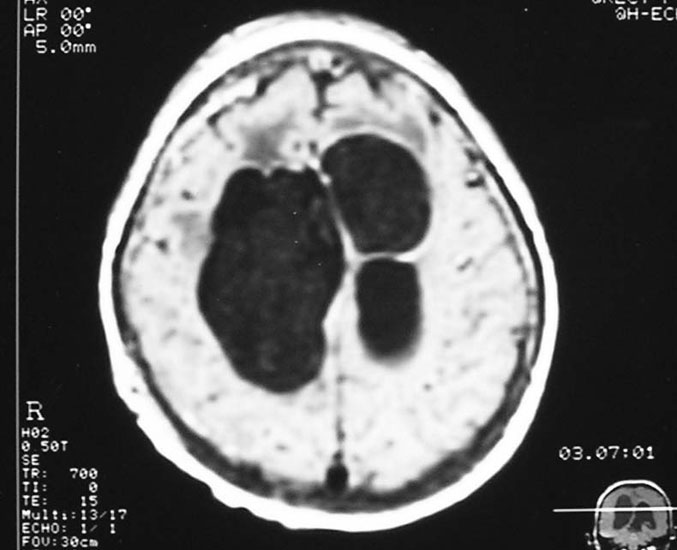

Hydrocephalus

Hydrocephalus is a common problem in the childhood, due to obstruction to the flow of cerebrospinal fluid (‘clear fluid within the brain cavities’). Child presents with an enlarging head, headache, vomiting, drop in school performance. MRI is required to diagnose hydrocephalus, and to ensure that there is no brain tumor causing obstruction. Treatment is insertion of ventriculoperitoneal shunt from brain to the abdomen. In older children, endoscopic third ventriculostomy too can be considered.